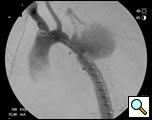

At our institution a dedicated CT angiogram of the chest was obtained to better define the morphology of the patient’s arch and aneurysm. This confirmed the finding of a saccular aneurysm just distal to the left subclavian artery takeoff. Because of the patient’s prior history of coarctation recurrence and repair, this was felt most likely to represent a pseudoaneurysm, possibly at the site of a patch repair. Aortic reconstructions of the CT angiogram showed no evidence for recurrence of the coarctation (Figure 2). There was, however, a size discrepancy in the diameter of the aorta above and below the aneurysm. The diameter of the aortic arch between the left carotid and left subclavian arteries was 13mm. The diameter of the descending thoracic aorta distal to the aneurysm was 23mm.